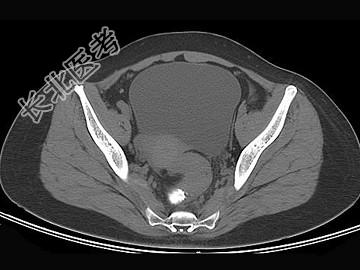

- 单项选择题女,67岁, 排便习惯改变,血便3月入院, CT检查如图所示,下列说法错误的是 ( )

A、直肠肠腔局限性增厚

B、其表面欠光整,边界欠清晰

C、可做直肠指检及活检以确定病变性质

D、此为直肠息肉

E、此为直肠癌